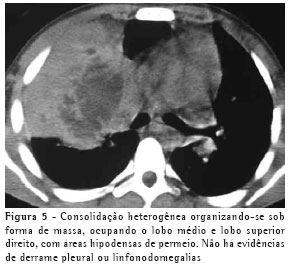

O achado de imagem mais freqüente, presente nos 7 pacientes, foi consolidação de contornos mal definidos (Figuras 1, 2, 3 e 4), sendo que 5 deles tinham broncograma aéreo de permeio, principalmente na periferia da lesão. Em 3 casos, a consolidação organizava-se sob forma de massa. Em 6 dos 7 pacientes foram observadas, no interior das consolidações, áreas irregulares de escavação, múltiplas em 5 e única em 1 paciente. Em um dos casos não se observou escavação, mas ele mostrava áreas hipodensas de permeio, sugestivas de necrose (Figura 5). Apenas um dos pacientes apresentou nível líquido no interior das cavidades.

A lesão escavada predominou nos lobos superiores, sendo 4 à direita e 1 à esquerda. Em um destes pacientes, ela acometia também o lobo médio. Em 2 casos, ela ocorreu nos lobos inferiores, 1 à direita e 1 à esquerda. Em 4 casos as lesões acometiam apenas os lobos citados, sendo portanto unilaterais. Nos outros 3, atingiam também, em menor intensidade, o pulmão contralateral. Em um caso, havia também escavação de paredes relativamente finas, multisseptada, sem nível líquido, localizada no lobo médio.

Na nossa casuística, o principal padrão de acometimento pulmonar foi o de consolidação com broncograma aéreo de permeio e escavação, presente em 6 pacientes, sendo as escavações múltiplas em 5 casos e única em 1. As consolidações tinham grandes proporções e contornos anfractuosos. Os broncogramas aéreos estavam localizados nas porções periféricas das lesões. O lobo pulmonar mais freqüentemente envolvido foi o lobo superior direito, acometido em 4 pacientes. A maioria dos trabalhos de revisão de casos confirma tais achados.(2,5) Alguns trabalhos relatam que, embora a escavação possa não estar presente no momento do diagnóstico, ela acaba por se desenvolver durante a evolução da doença.(4) Níveis líquidos no interior das escavações foram vistos em apenas um paciente na casuística estudada.